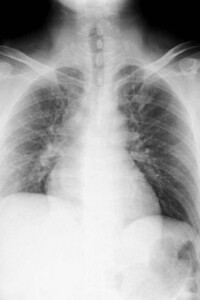

側弯症とは、背骨が左右に曲がり、ねじれを伴う状態を指します。程度の軽いものは自覚症状が少ないこともありますが、進行すると見た目の変化だけでなく、痛みや内臓の圧迫などにもつながることがあります。